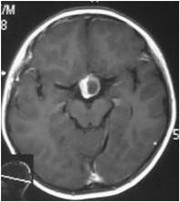

入院后行CT、MR检查,显示:鞍区及鞍上较大占位病变,考虑颅咽管瘤。遂于2010-08-11在全麻下行“鞍区及鞍上颅咽管瘤切除术”,术后病理:造釉细胞型颅咽管瘤。于2011-01-04开始给予三维适形放疗,总结量5040cGy/28F。放疗后,患者定期回院复查肿瘤复发征象。

2010年12月 术后4月(放疗前)